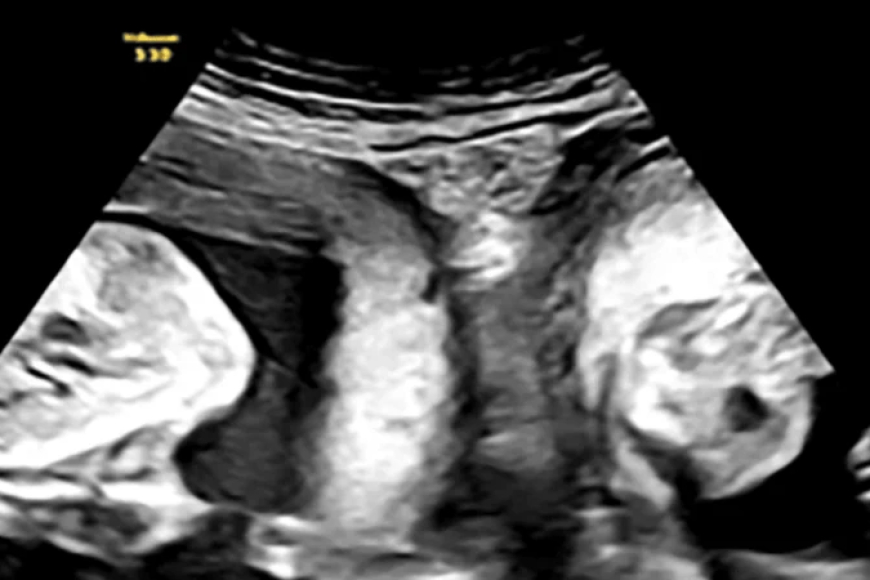

Umugore waremanywe umwihariko wo kugira nyababyeyi ebyi...

Umugore wo mu Bushinwa, waremanywe umwihariko wo kugira nyababyeyi ebyiri, yabya...